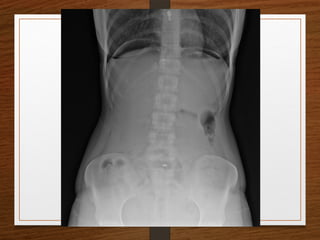

PNEUMOPERITONEUM

• Miss it and the patient may die

• Bilateral dark crescents of gas under both domes of diaphragm

• Erect posture

• Left lateral decubitus

• 1 ml of air is more than enough

Signs of pneumoperitoneum

• Double wall sign ( RIGLER’S sign )

• Football sign – centrally placed intraperitoneal free air

• Dome sign

• Cupola sign of air under the central diaphragm

• Silver’s sign – visualization of falciform ligament

• Continuous diaphragm sign

• Lucent liver sign – air overlying or outlining liver

• Doges cap sign – triangle of air outlinig morrison’s

pouch

• Inverted V sign - air in umbilical ligaments